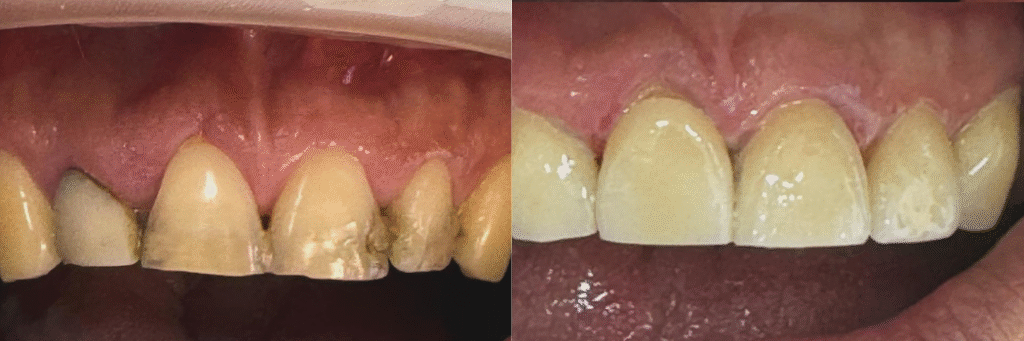

Múltiples carillas en estética desfavorable